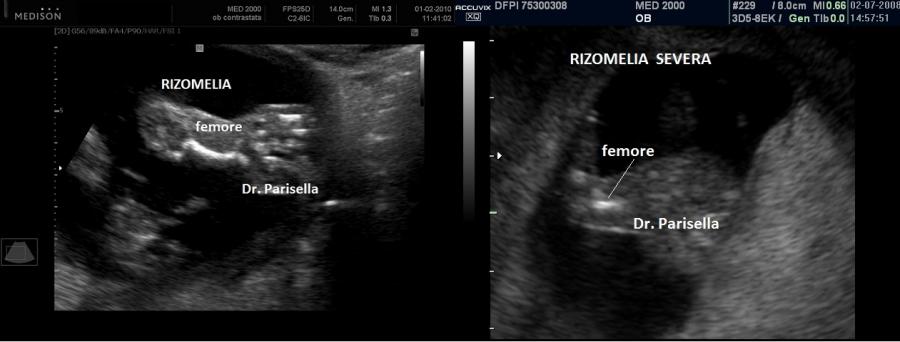

Le anomalie scheletriche sono sindattilia che interessa caratteristicamente il II-III dito dei piedi, polidattilia postassiale, rizomelia, pollici corti.